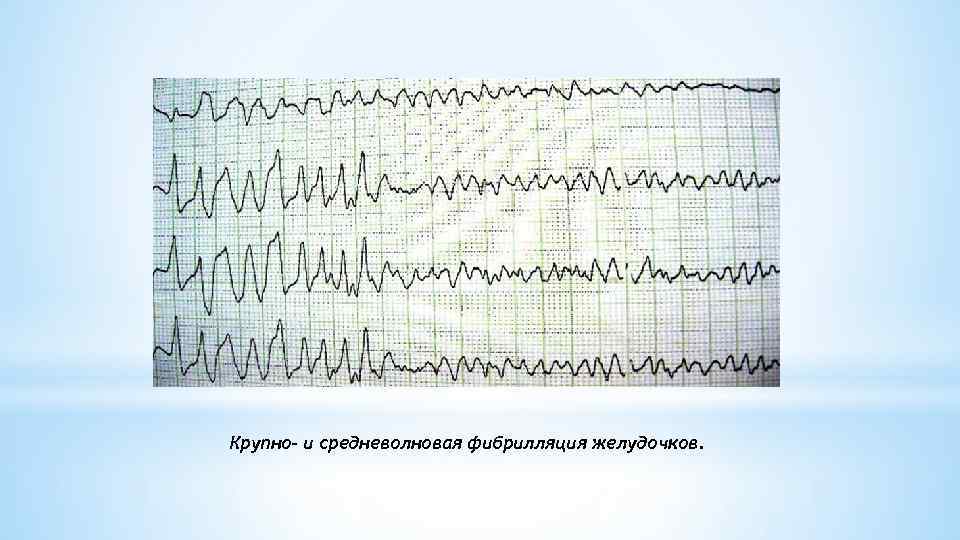

* Поскольку при возникновении фибрилляции желудочков насосная функция сердца прекращается, отмечается картина внезапной остановки кровообращения и клинической смерти. Больные теряют сознание, что часто сопровождается судорогами, непроизвольными мочеиспусканием и дефекацией. Зрачки расширены и не реагируют на свет. * Развивается диффузный цианоз, отсутствуют пульсация на крупных артериях — сонных и бедренных — и дыхание. Если в течение 4 мин не удается восстановить эффективный сердечный ритм, наступают необратимые изменения в центральной нервной системе и других органах. * При трепетании желудочков МОС, сознание и АД, обычно низкое, на короткое время могут сохраняться. В большинстве случаев, однако, этот неустойчивый ритм довольно быстро переходит в фибрилляцию желудочков. * На ЭКГ фибрилляция желудочков проявляется различными по амплитуде и продолжительности хаотическими волнами мерцания с недифференцирующимися зубцами и частотой более 300 в 1 мин. В зависимости от амплитуды этих волн различают крупно - и мелковолновую фибрилляцию. При крупноволновой фибрилляции амплитуда волн превышает 5 мм, при мелковолновой фибрилляции - не достигает этой величины.

* Поскольку при возникновении фибрилляции желудочков насосная функция сердца прекращается, отмечается картина внезапной остановки кровообращения и клинической смерти. Больные теряют сознание, что часто сопровождается судорогами, непроизвольными мочеиспусканием и дефекацией. Зрачки расширены и не реагируют на свет. * Развивается диффузный цианоз, отсутствуют пульсация на крупных артериях — сонных и бедренных — и дыхание. Если в течение 4 мин не удается восстановить эффективный сердечный ритм, наступают необратимые изменения в центральной нервной системе и других органах. * При трепетании желудочков МОС, сознание и АД, обычно низкое, на короткое время могут сохраняться. В большинстве случаев, однако, этот неустойчивый ритм довольно быстро переходит в фибрилляцию желудочков. * На ЭКГ фибрилляция желудочков проявляется различными по амплитуде и продолжительности хаотическими волнами мерцания с недифференцирующимися зубцами и частотой более 300 в 1 мин. В зависимости от амплитуды этих волн различают крупно - и мелковолновую фибрилляцию. При крупноволновой фибрилляции амплитуда волн превышает 5 мм, при мелковолновой фибрилляции - не достигает этой величины.

Крупно- и средневолновая фибрилляция желудочков.

Крупно- и средневолновая фибрилляция желудочков.

*Основные ЭКГ признаки фибрилляции желудочков • Отсутствие на ЭКГ типичной кривой с дифференцированными привычными зубцами P, Q, R, S и T. * • Вместо них регистрируются небольшие различные по величине (0, 1 -0, 3 m. V), неодинаковой формы волны фибрилляции. * • Расстояние между пиками волн различны. *Нет четкой изолинии; кривая фибрилляции приобретает хаотическую причудливую форму.

*Основные ЭКГ признаки фибрилляции желудочков • Отсутствие на ЭКГ типичной кривой с дифференцированными привычными зубцами P, Q, R, S и T. * • Вместо них регистрируются небольшие различные по величине (0, 1 -0, 3 m. V), неодинаковой формы волны фибрилляции. * • Расстояние между пиками волн различны. *Нет четкой изолинии; кривая фибрилляции приобретает хаотическую причудливую форму.